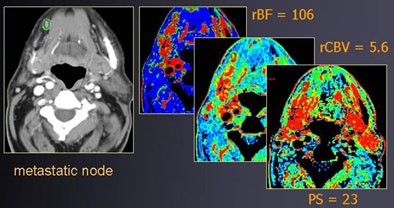

![]() |

| Round shape (contrast-enhanced CT, above) suggests suspect nodes in a patient with right-sided oral cancer. At perfusion CT (below), relative blood volume and permeability surface area product values of right lymph node are elevated compared to the contralateral side, showing hyperperfusion. Histopathology confirmed the malignancy. All images courtesy of Dr. Agneistsa Trojanowska. |